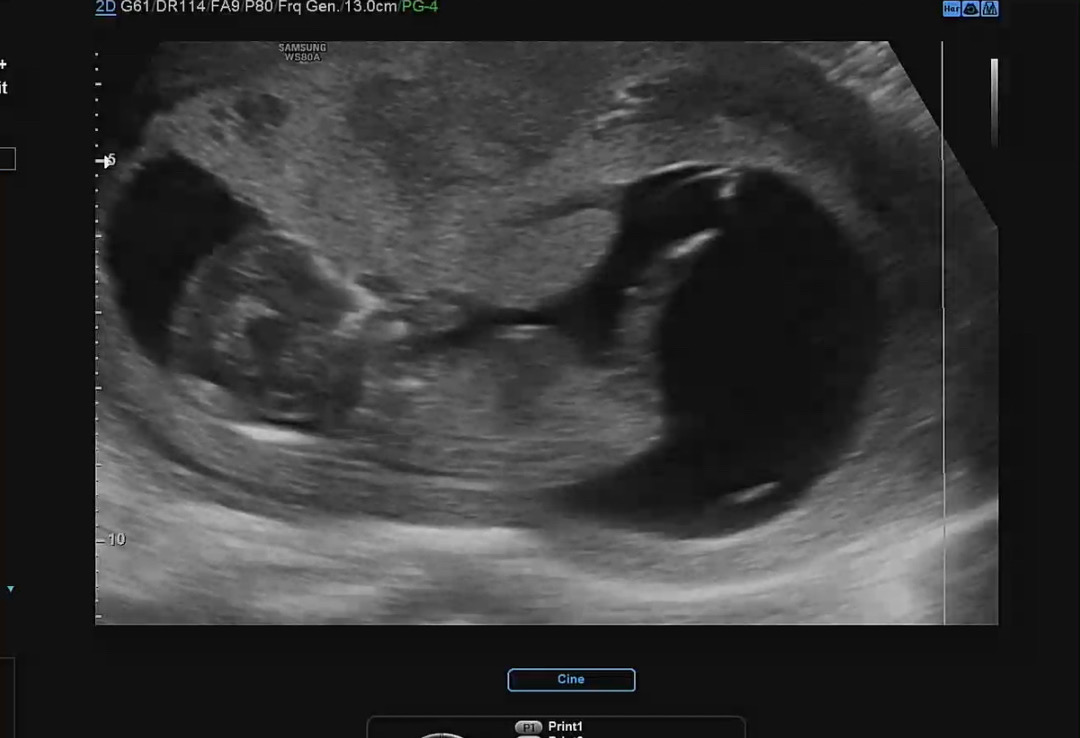

12주 2일 각도법 보이려나요ㅠㅠ

태반이 앞을 막고있어서 잘보이진 않지만 ㅠㅠ 보이려나욤